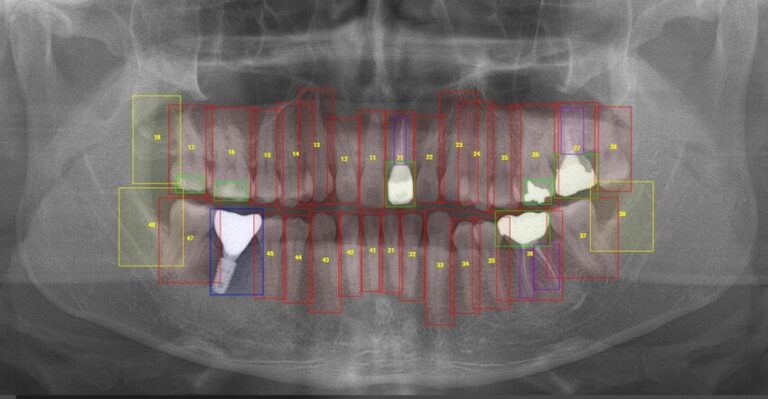

When it comes to your Dental AI model’s success, we at Nidaan offer a specialized service where our team of expert and experienced Oral and Maxillofacial Radiologists collaborates directly with your AI development process. We meticulously verify your dental report data, assist with the high-precision annotation of your datasets (CBCT scans, OPG X-rays, Cephalograms and TMJ x-rays), and aid in the machine learning refinement of your AI systems. This ensures that the data driving your models for all forms of detection, planning and prediction is clinically verified, accurately labeled, and ready for deployment.

Anatomical Segmentation

Precise outlining of teeth, nerves, jaws, sinuses, and airways.

Pathology Labeling

Accurate identification and classification of caries, cysts, tumours, and bone defects.